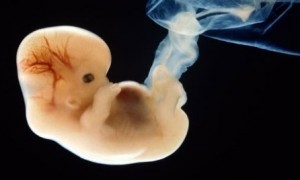

8 week old

Surgical abortions seldom take place before the sixth to seventh week of pregnancy. At this time, the developing embryo already has a heartbeat and brain waves. The majority of abortions take place in the eighth to tenth week. At this stage, the unborn baby is called a fetus. At this time, the unborn baby already has fingers and toes, a face, and all of her organs. The organs may be primitive – but they are all there. The fetus, at this stage, is obviously human – you can tell by looking at it that it is not a dog fetus or a cat fetus, but a human fetus. It is a human unborn baby in an early stage of development.